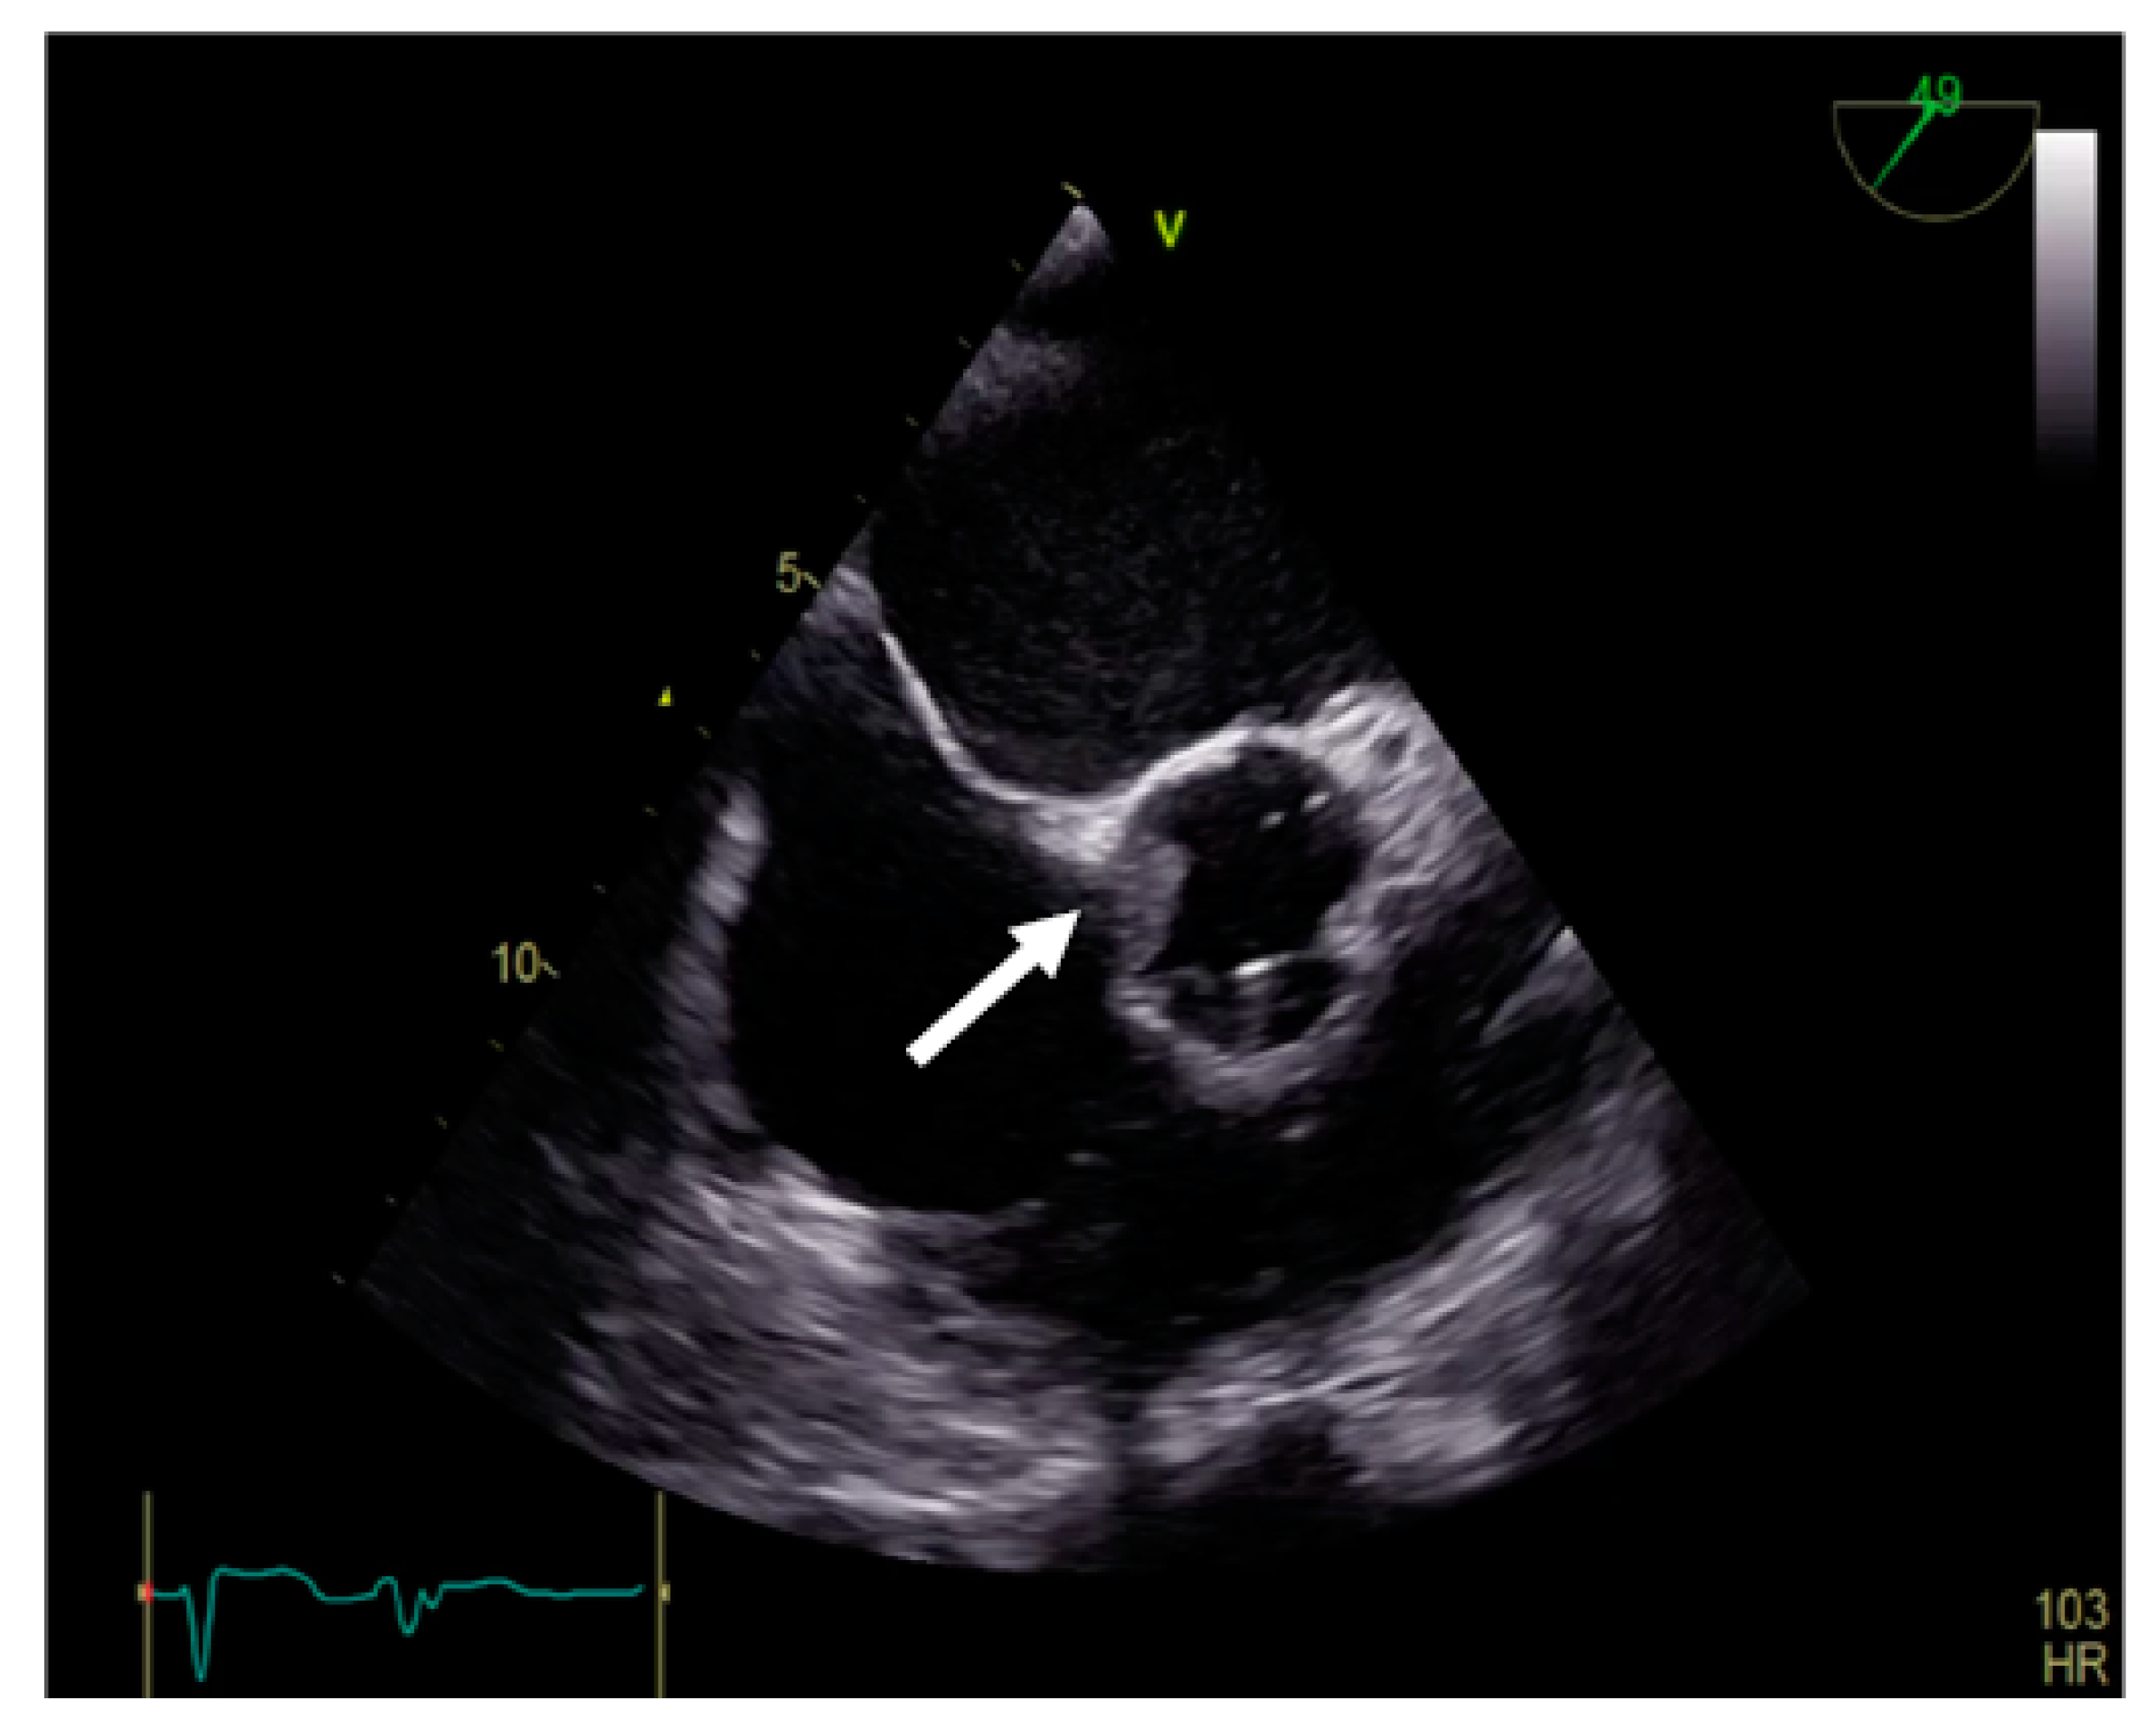

TEE is the gold-standard imaging method for MVT diagnosis, especially when mechanical prosthesis obstruction is caused by thrombosis [1,9,23,24,25,26]. Due to the proximity of the esophagus to the left atrium, the atrial face of any type of mitral prosthesis is accessible (Figure 4, Video S2, Supplementary Material). In the presence of obstructive thrombosis, the mobility of the discs is reduced or even blocked [23,24,27].

Figure 4.

TEE. Thrombus on the atrial side of mechanical mitral prosthesis (arrow).